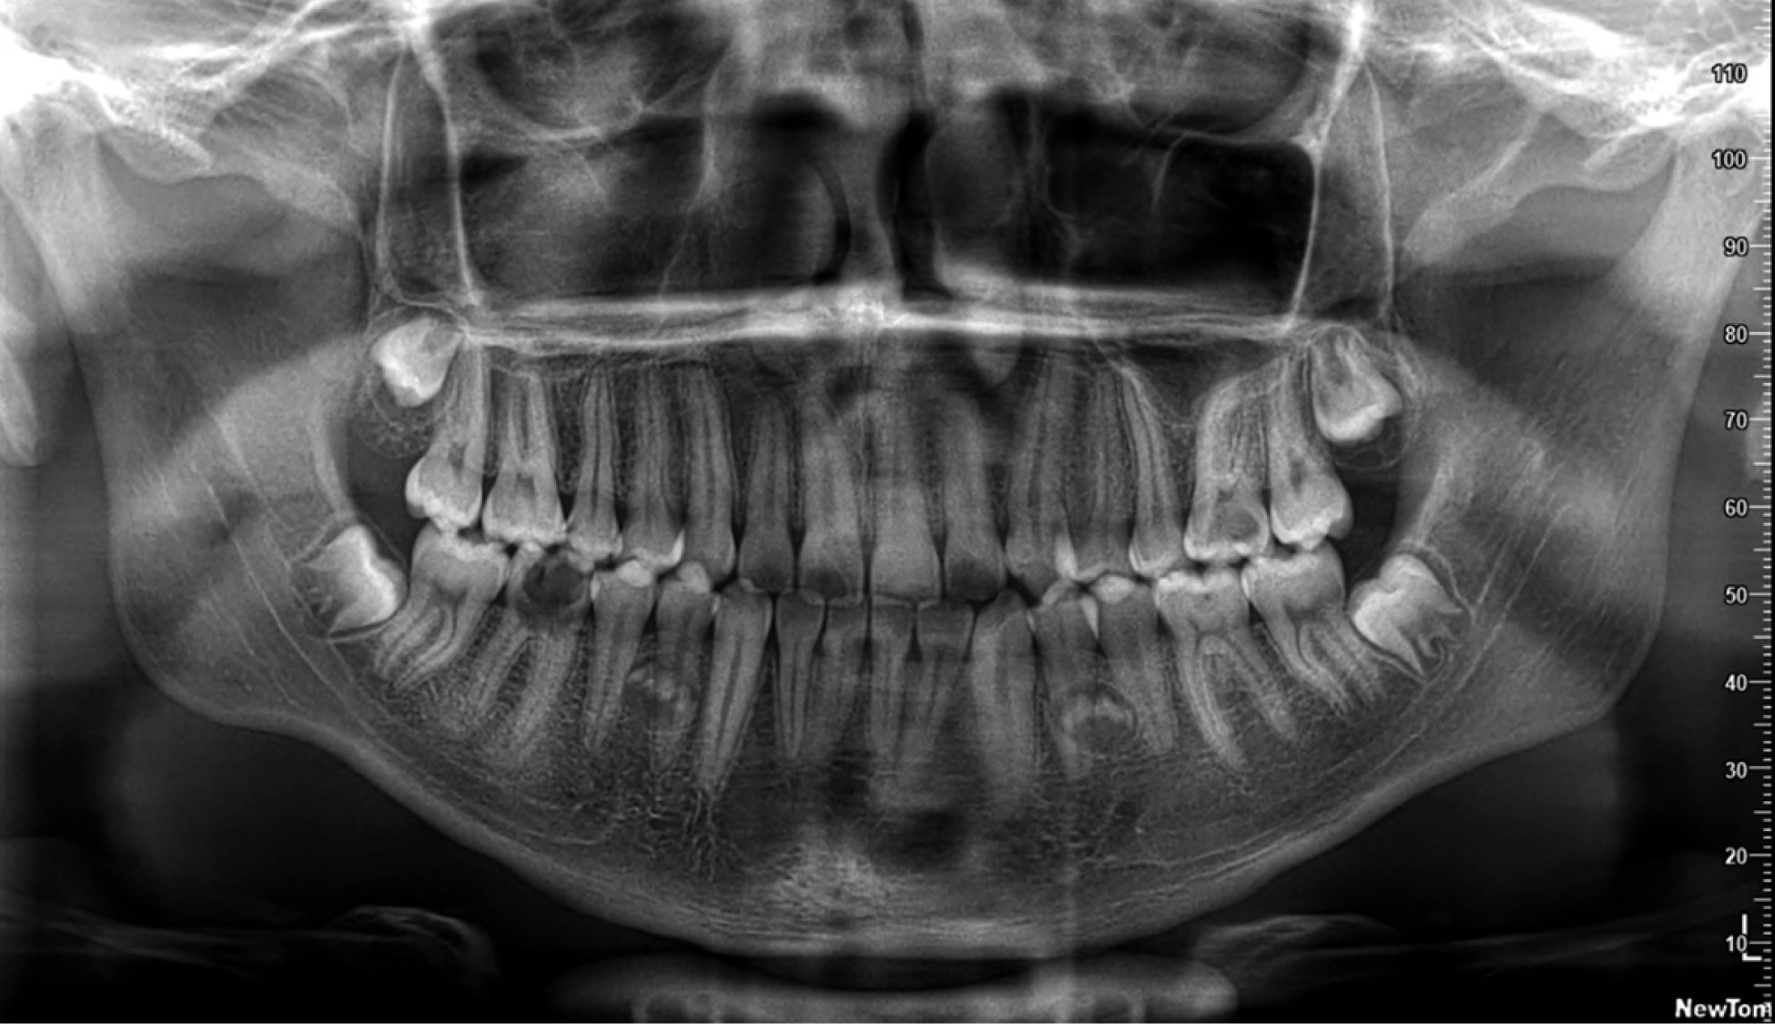

Supernumerary teeth are additional dental organs that exceed the normal number. They can present as single or multiple, unilateral or bilateral, and sometimes may be located anywhere in the dental arch, with a mandibular preference. They have the potential to cause problems with the eruption and alignment of normal dentition, which is why their treatment has often been a subject of debate. This case report describes the surgical approach of a 17-year-old male patient with dental germs present in the lower arch, located bilaterally between the premolars. The treatment plan consists of the extraction of the supernumerary tooth in quadrant 3, using various digital tools to design a surgical guide. The objective of this case is to present a surgical protocol for the extraction of a supernumerary tooth using a digital workflow.

Figure 1